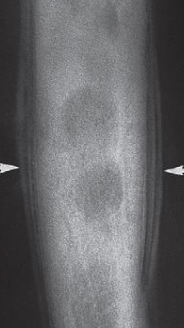

- Plain X-ray

- Electric shock or epileptic seizure

- ‘lightbulb’ appearance of the humeral head.

- Posterior dislocation of the shoulder

Fracture of the neck of the humerus (black arrows)

The greater tuberosity is also fractured (white arrow)